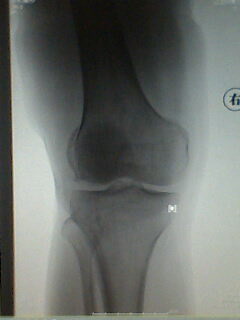

标题: X5658:膝关节改变?!

中年男性,外伤,疼痛!

股骨下段骨软骨瘤。撕脱性骨折

支持考虑骨软骨瘤,髁上突在肱骨内髁上方.本例股骨外髁关节面似有异常,但是可以是与髌骨重叠构成,必要时加照正位(稍内斜一点把髌骨让开)

宽基底与股骨干相连,背离关节面,支持考虑股骨下段外生骨疣

第二楼的回答是全面和正确的!

髌骨向外下移位,股骨下段骨软骨瘤。